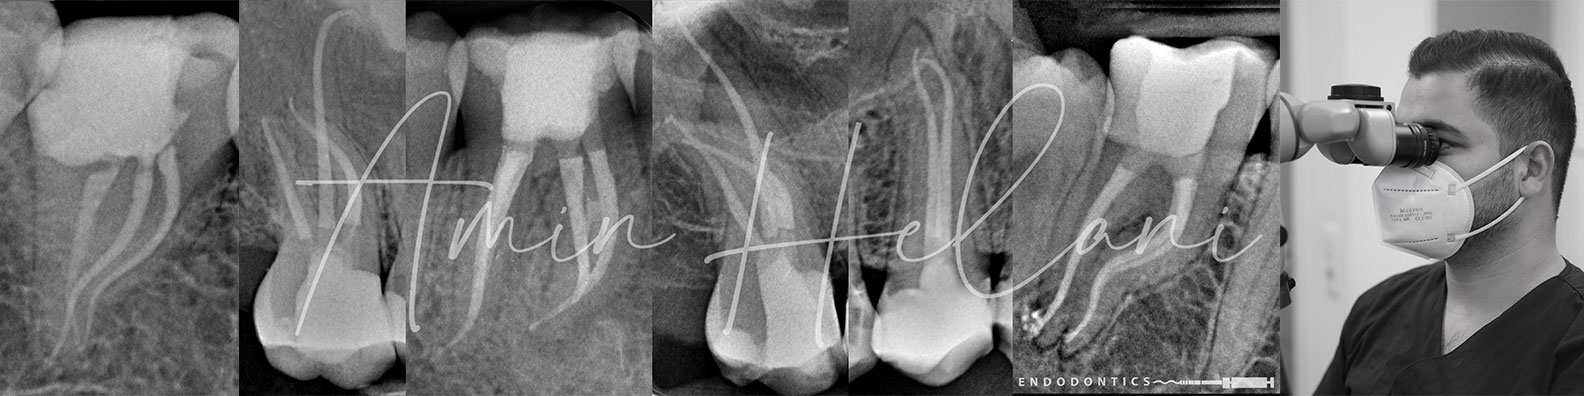

als spezialisierter Endodontologe unterstütze ich Sie dabei, die Zähne Ihrer Patienten langfristig zu erhalten. Alle Behandlungen werden unter dem Operationsmikroskop durchgeführt, um maximale Präzision zu gewährleisten.

- Wurzelkanalbehandlungen und Revisionen

- Entfernung von Fragmenten/Stiften

- Verschluss von Perforationen

- Apexifikationen und mikroskopische Wurzelspitzenresektionen